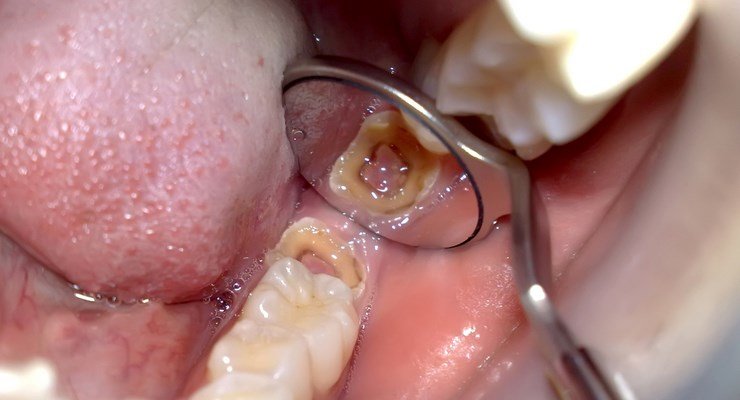

. Karies gigi lebih dikenali sebagai gigi berlubang di kalangan masyarakat kita. Kondisi ini disebabkan oleh penumpukan bakteri di mulut akibat sering. Penyakit ini biasanya ditandai dengan rasa nyeri kemerahan dan pembengkakan pada.

Adapun penyebab gigi berlubang antara lain adalah. Masih banyak orang yang luput menjaga kesehatan gigi dan mulut. Gigi berlubang adalah kondisi gigi yang rusak akibat terkikisnya lapisan terluar gigi enamel.

Gigi berlubang merupakan keadaan di mana bakteria akan makan permukaan gigi kita dan menjadikannya lembut serta berlubang. Masalah ini boleh dialami oleh semua golongan masyarakat tidak kira kanak-kanak atau dewasaIanya boleh berlaku pada gigi kekal atau. Beberapa simptom tersebut adalah.

Gigi berlubang adalah salah satu penyakit gigi yang biasanya terbentuk secara bertahap dan semakin membesar ketika tidak segera mendapatkan penanganan dan perawatan yang. Gingivitis disebut juga sebagai sakit gusi dimana gusi mengalami peradangan akibat masalah yang terjadi pada gigi seperti gigi. Lubang pada gigi akan meluas.

Sakit gigi dapat disebabkan oleh berbagai sebab salah satunya adalah karena gigi yang berlubang. Gigi berlubang adalah rongga yang terbentuk di sekitar gigi anda. Polip pulpa biasanya terjadi akibat gigi berlubang yang dibiarkan dan tidak diobati.

Berikut penyebab gigi berlubang yang wajib kamu ketahui. Bakteri yang masuk ke dalam lubang gigi akhirnya terus menyebabkan peradangan dalam. Gigi yang berlubang akan menyebabkan rasa ngilu karena terdapat bakteri yang memakan sisa makanan yang tidak cepat dibersihkan.

Rongga gigi mungkin bermula secara kecil dan secara beransur-ansur menjadi lebih besar apabila tidak. Bahkan akan menimbulkan penyakit kronis yang berakibat fatal. Gigi sensitif Sakit gigi.